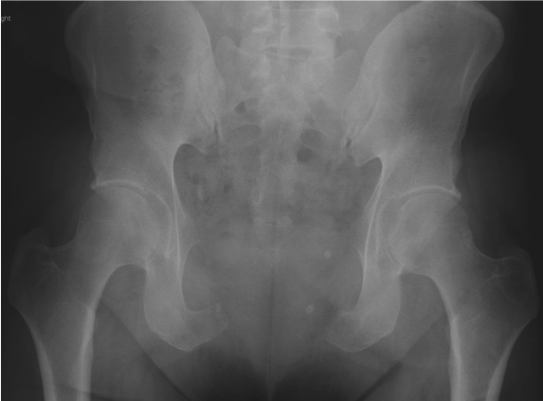

During the operation, a transverse incision was utilized to dissect down to bilateral pubic rami and the symphysis. The attachments of the rectus abdominis muscle were divided from the pubis, and neurovascular structures were carefully preserved while dissecting the tumor. Four bone cuts involving bilateral superior and inferior pubic rami were designed under fluoroscopic guidance and performed successfully without disrupting the adjacent joints (Figure 2). The resected bone and tumor specimen was sent fresh to pathology for analysis. The bladder, prostate, and urethra were carefully visualized and appeared uninjured. To reconstruct the residual 10 × 15-cm defect, a biologic dermal mesh (XenMatrix) was shaped to serve as an underlay at the lateral defect and a bridge in the central portion. The mesh was secured to the rectus muscles superiorly, pubic fascia inferiorly, and inguinal fascia laterally.

Figure 2. Pelvic radiograph taken 1 month postoperatively demonstrating the boundaries of the surgical resection. Bilateral superior pubic rami and pubic symphysis were resected with preservation of the sacroiliac and hip joints.